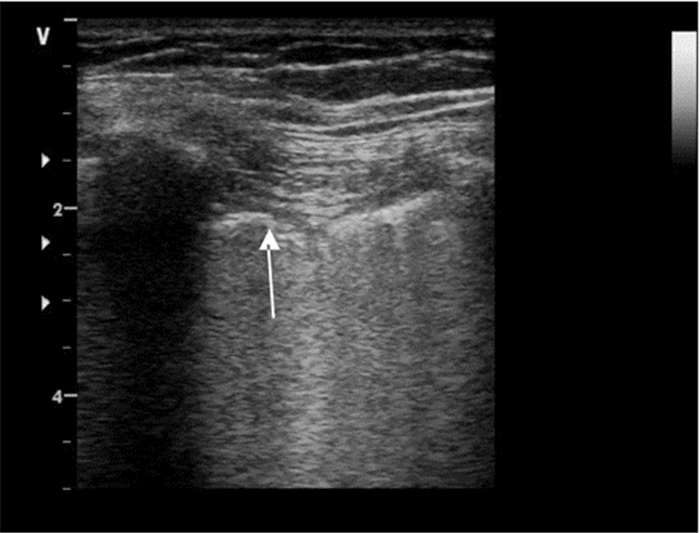

2.2.5 肝样变、碎片征大片肺实变时,实变肺组织呈现类似肝实质样软组织回声(图 12)。小片肺实变表现为不规则的碎片状强回声,即“碎片征”(图 13)。研究显示超声对厚度大于20 mm的肺实变检测阳性率较高,其总体敏感度和特异度分别为90%和98%。

| 图 12 大片肺实变:箭头示肺组织呈软组织回声改变 |